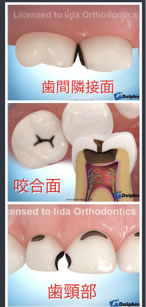

虫歯ができやすい場所は、以下の3つです。

①歯間隣接面 : 歯と歯の間です

②小窩裂溝 : 臼歯の咬合面の溝です

③歯頚部 : 歯と歯肉の境目です

次に、部位は

①上の前歯4本、上下の奥歯の歯と歯の間(歯間隣接面)

②上下の奥歯の小窩裂溝

③上下の犬歯、小臼歯の歯頚部

④上下の奥歯の頬側の歯面